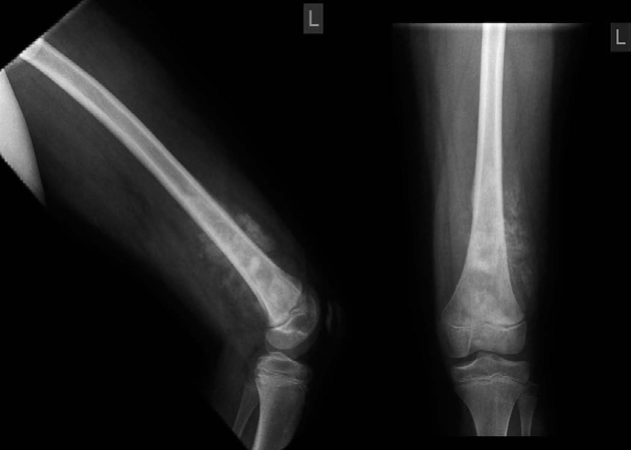

Orthopaedic oncology Structured oral examination question 2: Enchondroma Figure 7.2 Enchondroma. EXAMINER : T…